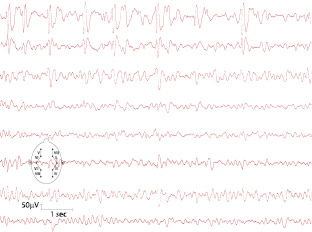

Dies ist die häufigste Form kindlicher fokaler Epilepsien. Das Manifestationsalter liegt zwischen dem 2. und 12. Lebensjahr. Die Anfälle treten überwiegend im Schlaf auf. Charakteristisch sind Missempfindungen im Bereich von Mundhöhle, Zunge und Gesicht, gefolgt von hemifazialen Kloni unter Einbeziehung der Kaumuskulatur (typisch vermehrter Speichelfluss). Das Bewusstsein ist in der Regel erhalten, die Kinder können aber nicht sprechen. Das EEG zeigt zentrotemporale „sharp waves“ (Abb. 7.1). Die Anfälle sistieren mit Beginn der Pubertät.